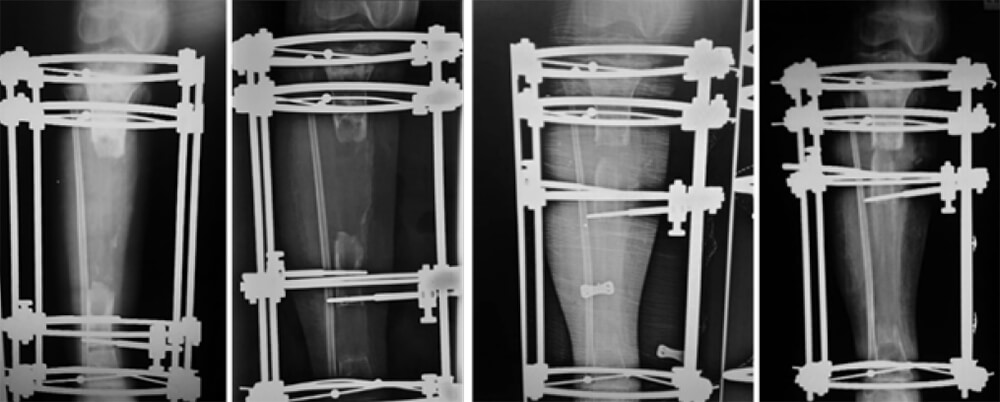

En vista de la buena evolución clínica posterior a la segunda intervención, la paciente es egresada y controlada sucesivamente por 4 semanas en la consulta externa, posterior a lo cual se decide realizar el procedimiento reconstructivo del defecto óseo mediante transporte óseo circular tipo Ilizarov CITEC- ULA® (Mérida, Venezuela). El tamaño del defecto óseo se cuantificó en 12cms. 4 meses después de iniciar su enfermedad actual, sin evidencias de recidiva del proceso infeccioso se decide llevar a quirófano para realizar la colocación del dispositivo para el transporte caudo-cefálico (Figura 4).

Figura 4. Secuencia de evolución del transporte óseo para la reconstrucción de 12cms de la tibia.

Una vez culminado el transporte y la fase de corticalización y observarse consolidación se retiró el aparato. Los resultados funcionales y radiológicos finales fueron evaluados de acuerdo a los Criterios de Paley (Tabla 1) (6). La paciente alcanzó resultados funcionales y radiológicos excelentes (Figura 5).

Figura 5. Resultados radiológicos y funcionales finales del proceso reconstructivo.